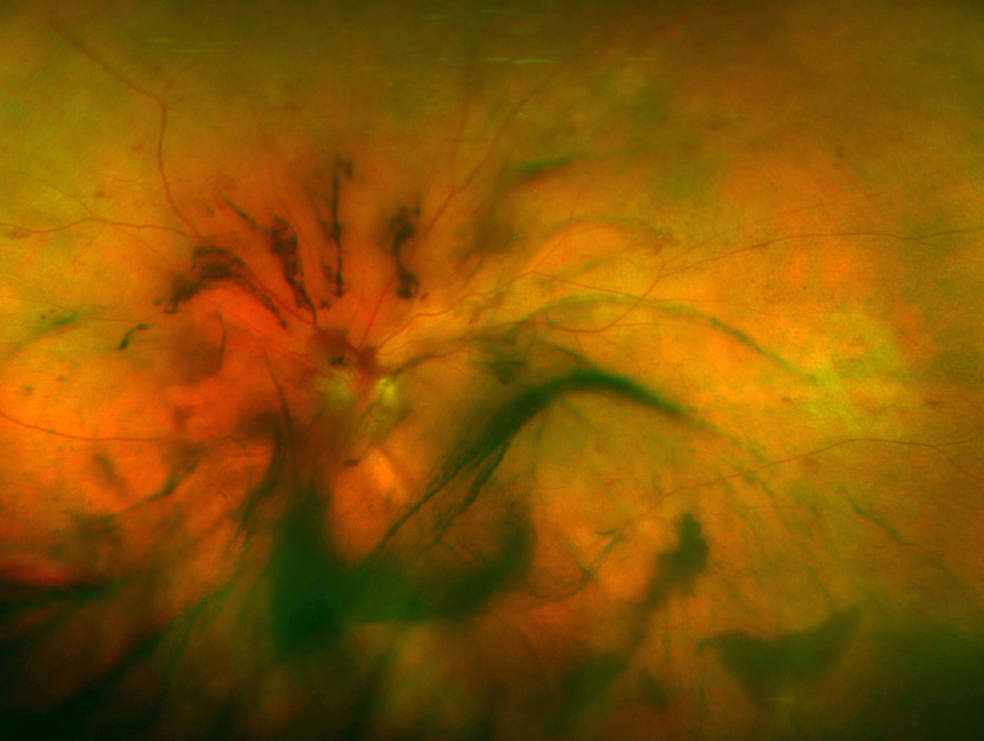

Diabetic Retinopathy Mr Ellabban Eye Surgery Yorkshire & Hull Laser Eye Surgery Yorkshire Clinic the three main types of laser eye surgery are lasik, lasek and relex smile. Lasik is the most popular type of laser eye surgery. laser eye surgery is the variety of surgical procedures that involve an eye surgeon (ophthalmologist) using a. from leading laser eye surgery & lens replacement to cataract and other medical treatments, optegra is. Laser Eye Surgery Yorkshire Clinic.